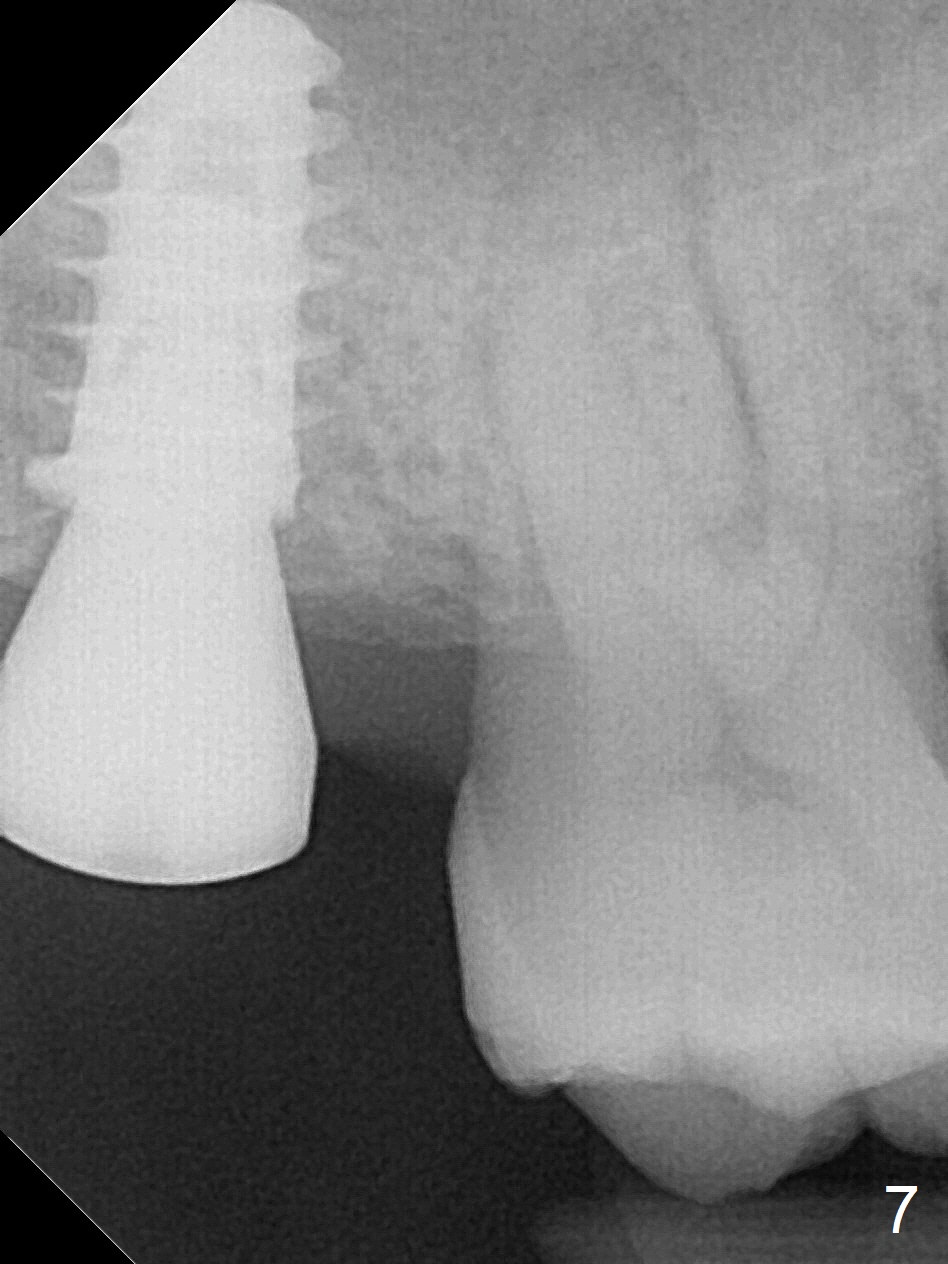

Since the ridge at the site of #2 is wide (Fig.1), Magic Split is used for access and bone density determination. In fact it enters for 9 mm (gingival level), followed by Magic Expander (ME) 3 mm (Fig.2 *). The center of the latter is 3.9 mm from the distal surface of the tooth #3. Lindamann bur is used to move the osteotomy distal, followed by sequential use of MEs until 4.3 mm one. When a 5x9 mm dummy implant is placed, its center is somewhat mesial (Fig.3 brown line). What needs to be done is change the trajectory to the red line so that the coronal end of the definitive implant (5.5x9 mm) will be placed evenly subcrestal (Fig.4,5). It is what happens, although slightly too subcrestal. Insertion torque is <35 Ncm; a 6x4 mm healing abutment is placed. ME 4.8 mm has to be tapped for 13 mm from gingival margin in order to let the implant penetrate the sinus floor. IBS implants seem to lack self tapping ability. Its tap drills should possess this capacity. Allograft/autogenous bone (harvested from dummy implant) is placed prior to implantation. The patient returns for impression 6 months postop (Fig.6,7; #4). A 5x4(3) mm abutment is placed; its height is reduced as well as the opposing supraerupted tooth (Fig.5) prior to impression.